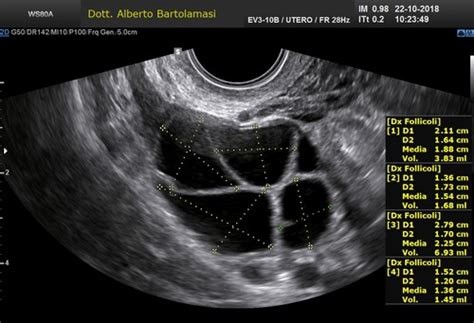

La diagnosi si basa sull'osservazione clinica e sull'ecografia transvaginale, che permette di visualizzare il sacco gestazionale (dalla quinta settimana) e l'embrione (dalla sesta settimana). In caso di incertezza, il medico programmerà una valutazione seriale dei livelli di beta-hCG, l'ormone della gravidanza, per monitorare l'evoluzione della gestazione.